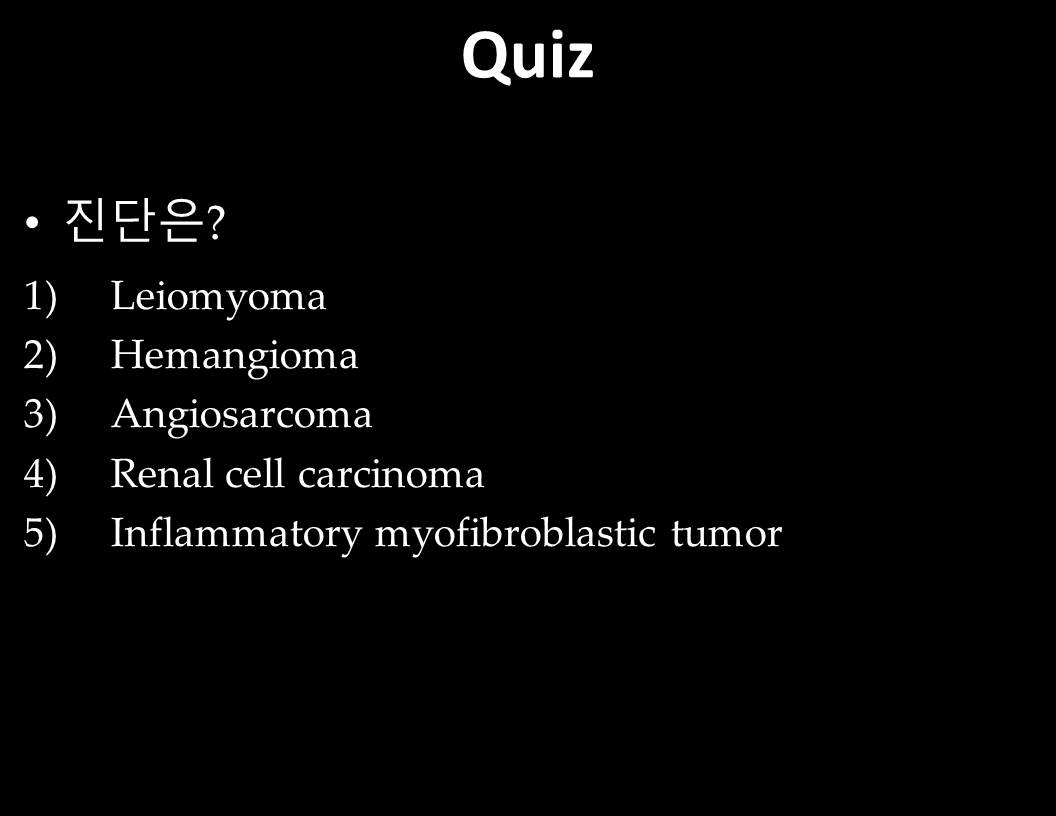

| 진단은? |

| Diagnosis | (retroperitoneal) angiosarcoma | ||